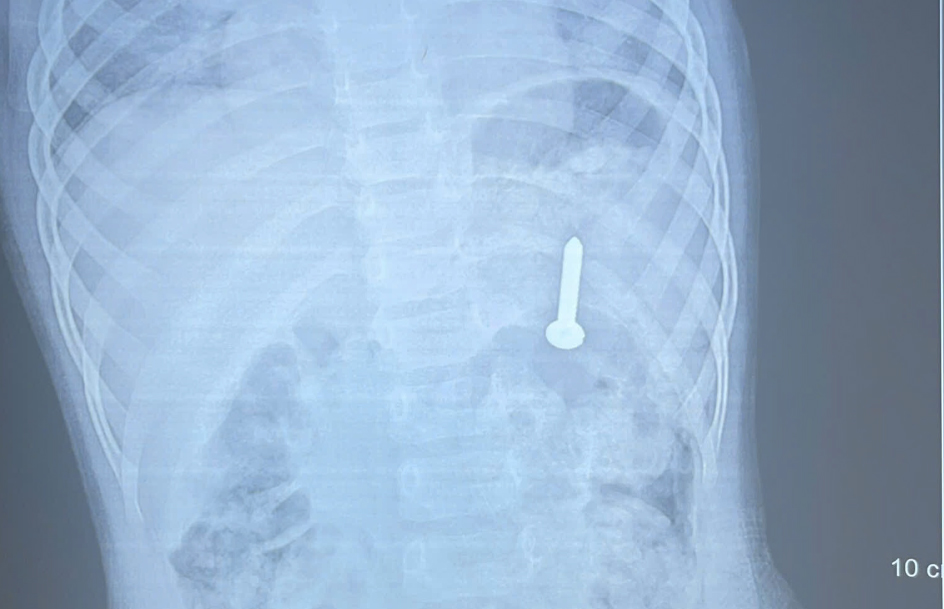

On 14/4, Quang Tri Provincial General Hospital announced that an X-ray confirmed a foreign object was lodged in the girl's stomach. Doctors warned that if not addressed promptly, the object could lead to perforation of the digestive tract, hemorrhage, and other dangerous complications.

The screw in the girl's stomach. Photo: Hospital provided |